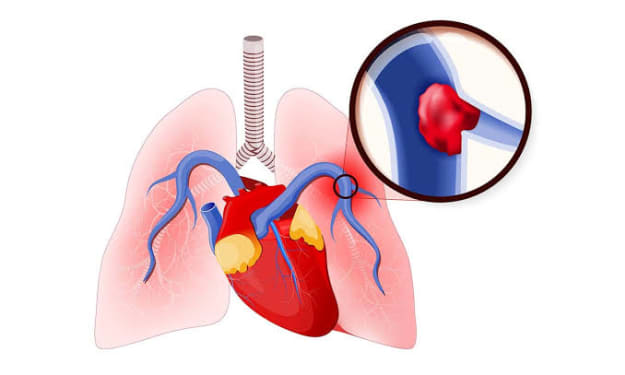

Harrison is known for having the shortest term. He went into the office at age 68, on March 4, 1841, and died of pneumonia on April 4. He is also well known for another issue that has not been substantiated, yet the rumors persist.